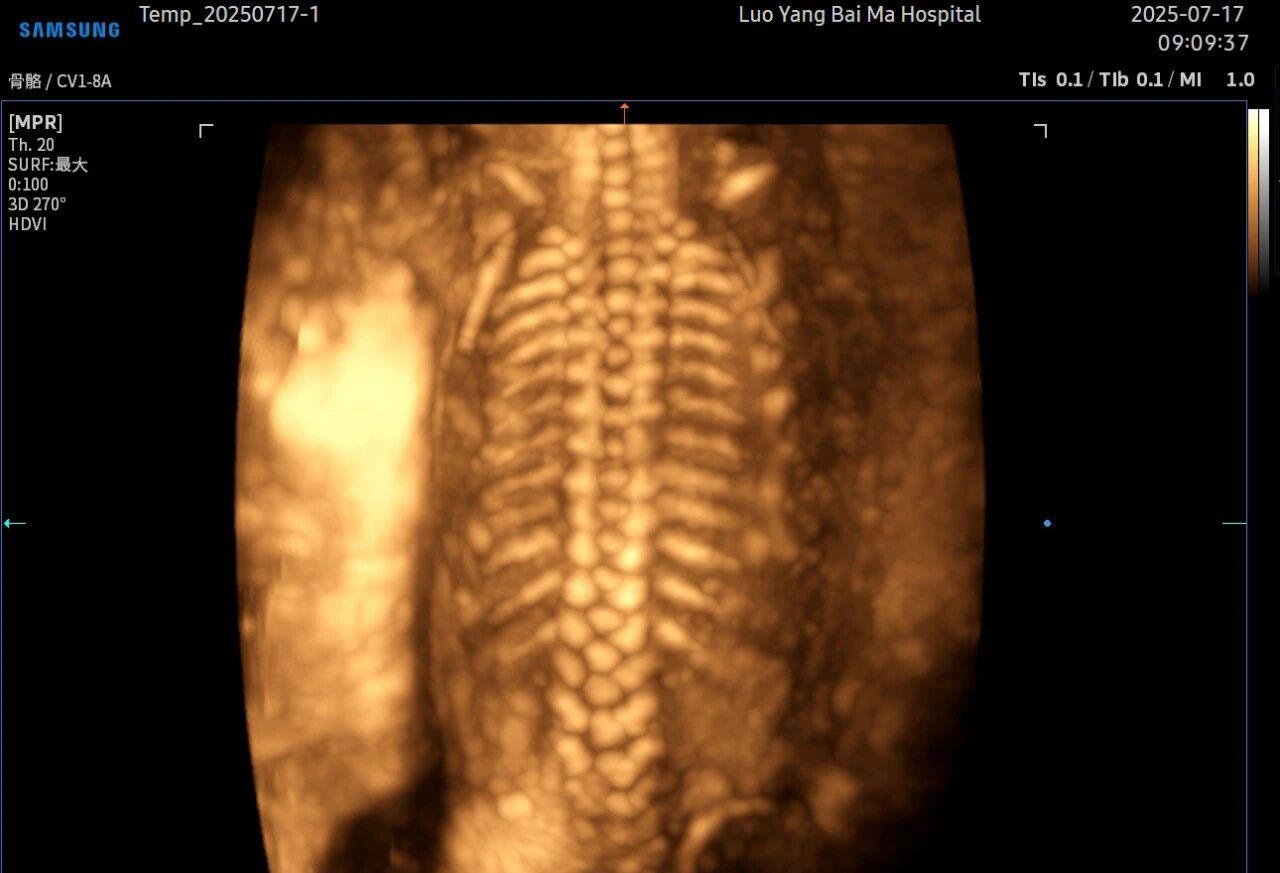

2. 全方位、多角度的“360度”观察

传统超声检查有时会因为胎儿体位、羊水量等因素的限制,导致某些部位观察不清。5D智能彩超技术能够实现对目标结构进行360°全方位、多切面的自由旋转观察。医生可以像“雕塑家”一样,从任意角度审视胎儿的解剖结构,尤其对于形态复杂的心脏、颅脑和脊柱等部位,这种能力可以极大弥补单一平面的局限性,帮助医生更全面地评估其发育状况。